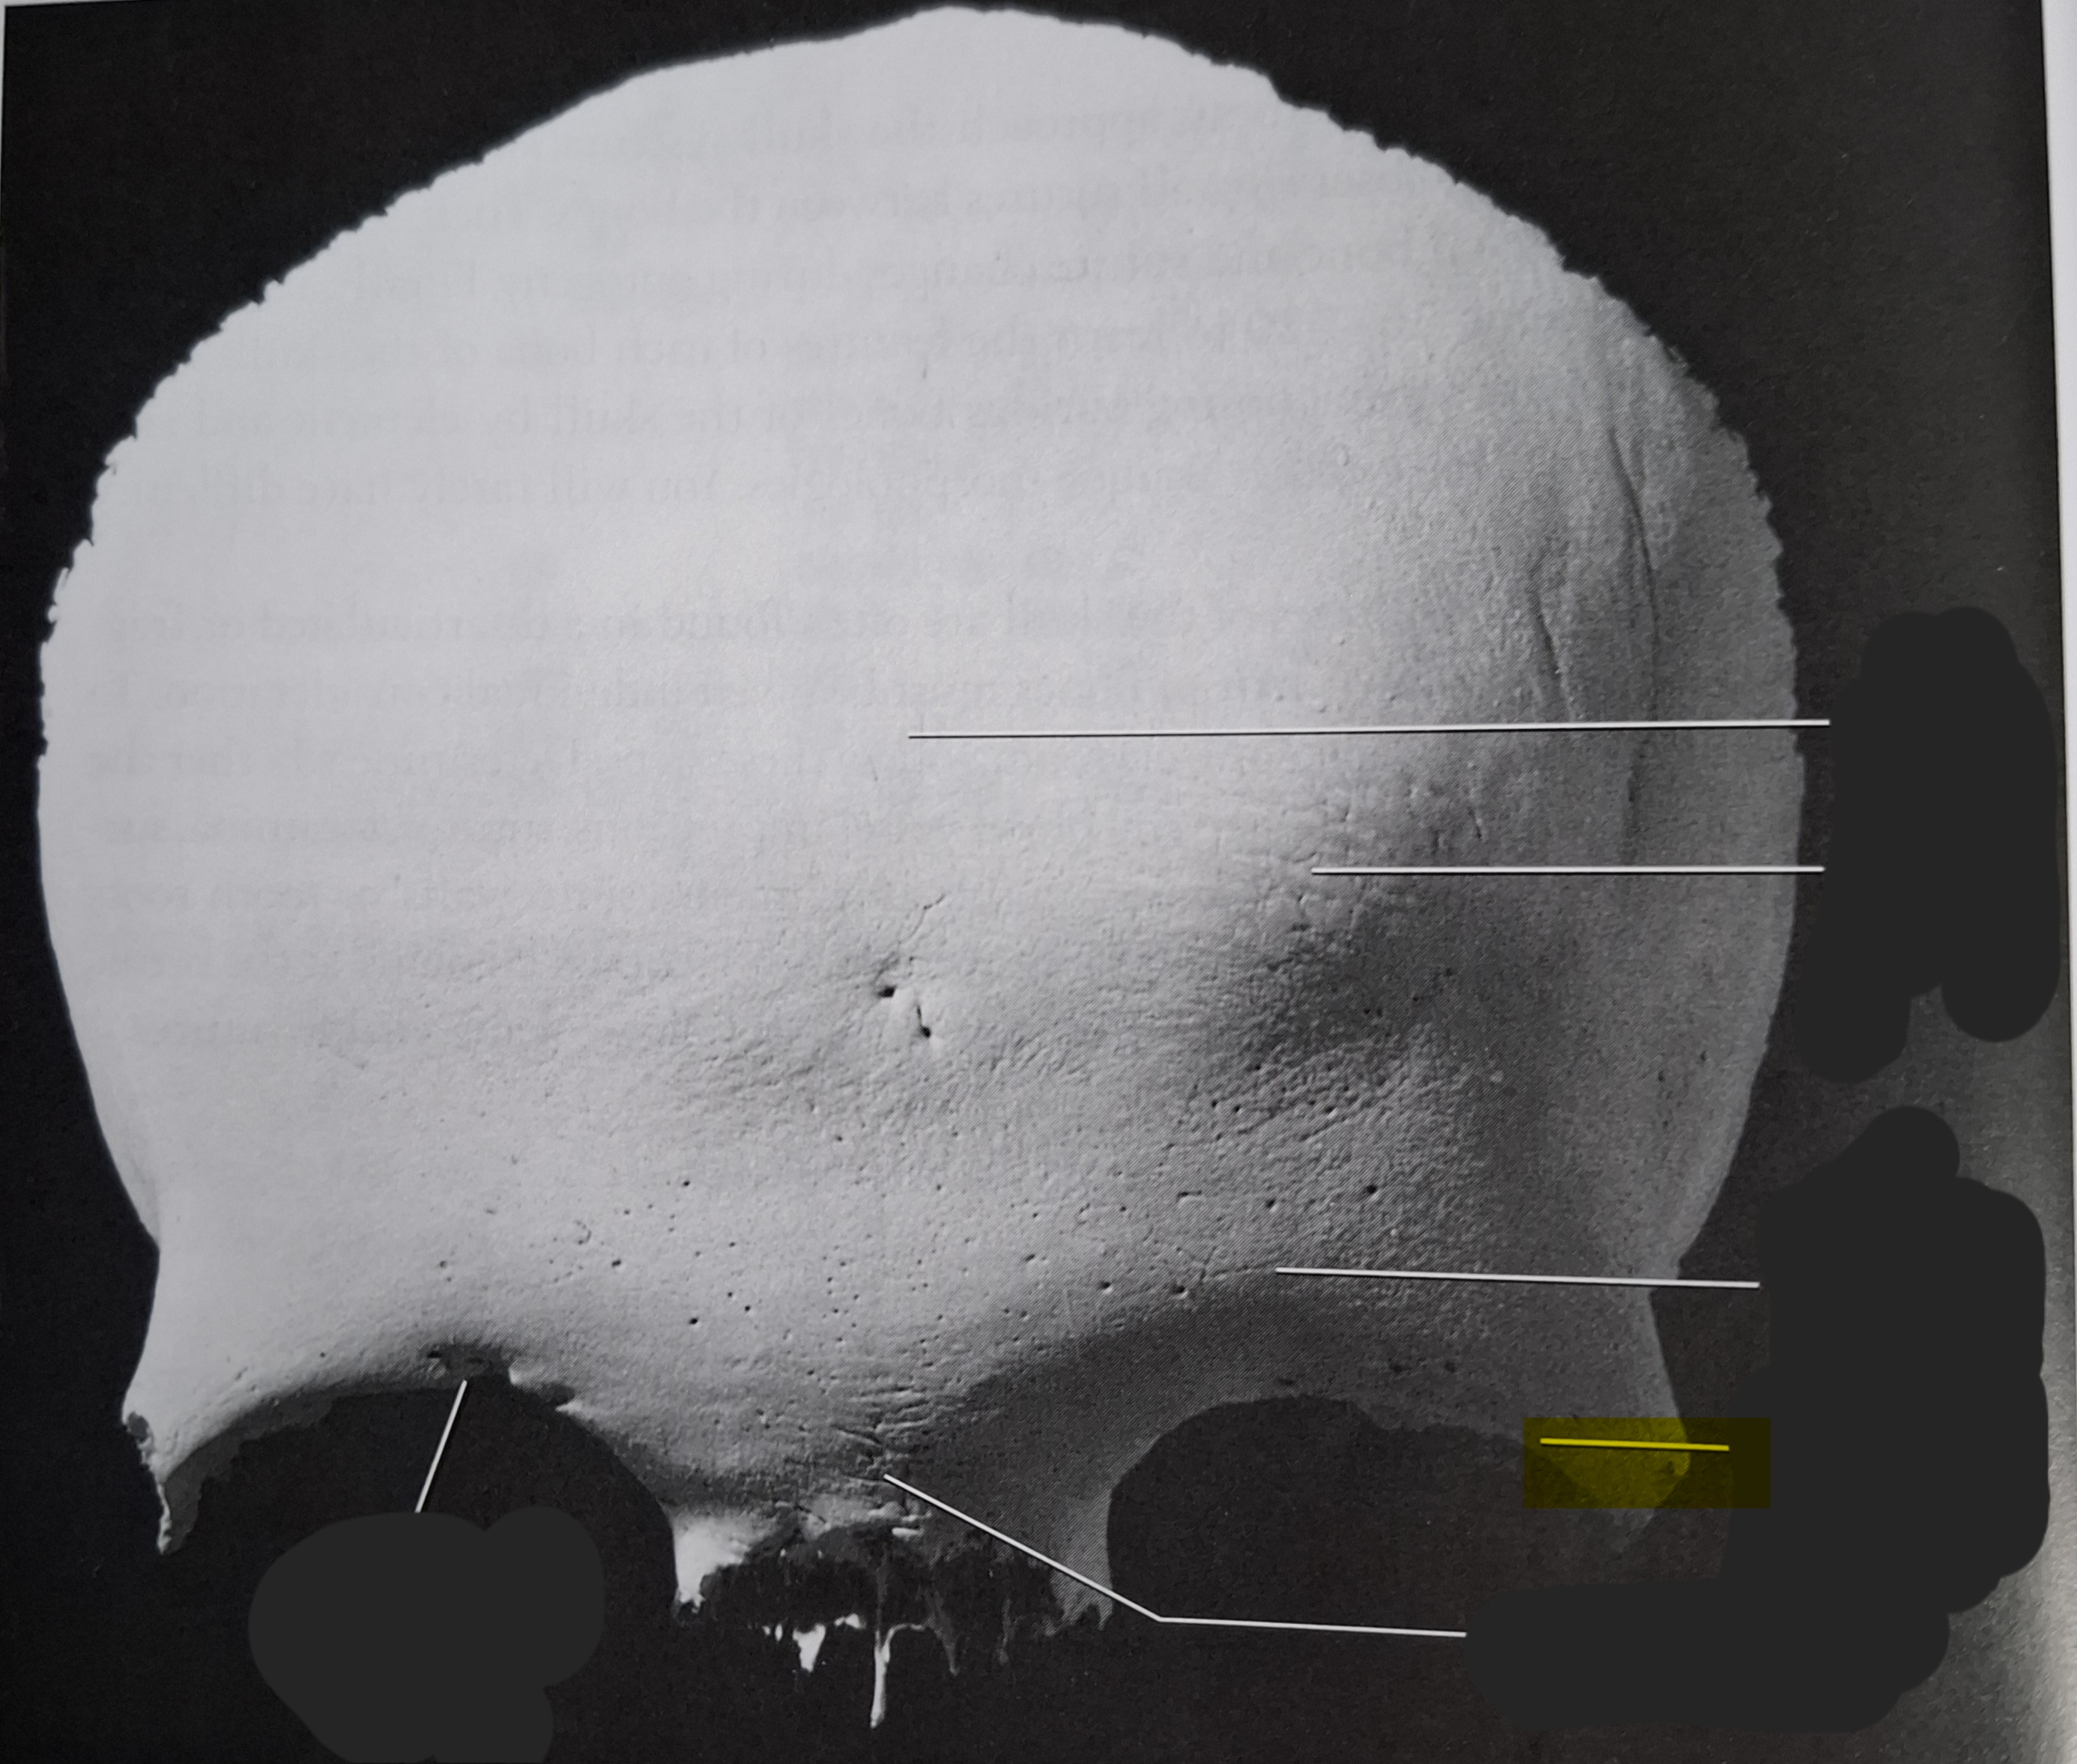

Occipital

Superior nuchal line

Inferior nuchal line

Foramen magnum

Occipital condyle

External occipital protuberance

Basilar part

Parietal

Superior temporal line

Inferior temporal line